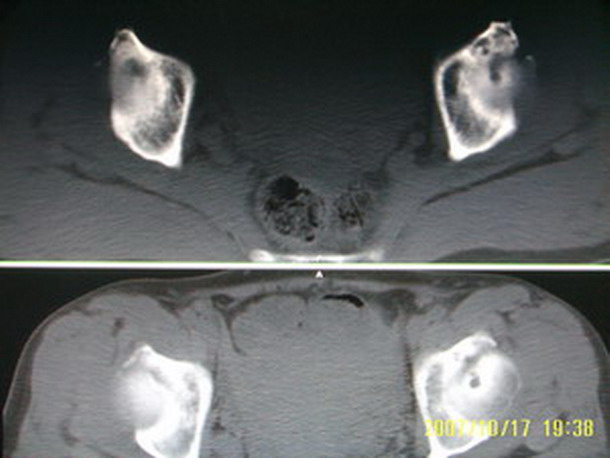

标题: CT10352:女,45岁,股骨头病变,如何诊断? [打印本页]

标题: CT10352:女,45岁,股骨头病变,如何诊断?

股骨头病变,如何诊断?

患者女,45岁,左髋部行走疼痛一年,无外伤史,无感染史。x片示囊状骨透亮区

左侧股骨头变形,密度增高,局部塌陷。多考虑:股骨头缺血性坏死伴退变!

左侧股骨头塌陷,其内囊变硬化,骨纹理改变考虑:左侧股骨头坏死及蜕变.

股骨头形态尚可,骨皮质环厚度及完整性可,病灶区以外骨质尚未见明显异常,临近髋臼骨质亦可见类似改变,考虑退变性关节面下囊变可能性大,骨样骨瘤等不排除,

两侧髋臼结构发育不良伴退行性改变.不除外色素沉着绒毛结节性滑膜炎.

支持成人髋臼发育不良继发髋关节退行性变

髋关节发育不良,左髋关节退变,左髋关节邻关节囊肿

股骨头形态尚可,骨皮质环厚度及完整性可,病灶区以外骨质尚未见明显异常,临近髋臼骨质亦可见类似改变,考虑1.动脉瘤样骨囊肿,2.股骨头缺血坏死,

股骨头形态尚可,骨皮质环厚度及完整性可,病灶区以外骨质尚未见明显异常,临近髋臼骨质亦可见类似改变,考虑退变性关节面下囊变可能性大

双侧股骨头形态都欠规整,外形欠光滑,尤以左侧明显,考虑双侧髋臼发育不良并退行性变